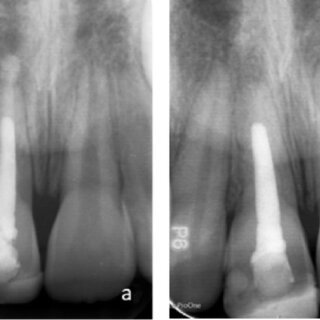

Présentation : Mme Faure, 52 ans, consulte après avoir ressenti une douleur intense lors d’un traitement endodontique débuté chez son précédent praticien. La radiographie révèle une perforation au niveau de la furcation de la première molaire supérieure droite (16), survenue lors de la mise en forme canalaire. La dent est asymptomatique au repos mais douloureuse à la percussion verticale.

Problématique identifiée : Une perforation furcationnelle non traitée entraîne à terme une perte osseuse localisée, une contamination bactérienne du parodonte de soutien et, sans traitement, la perte de la dent.

Prise en charge : Sous digue, les canaux sont finalement obturés à la gutta-percha. La perforation est localisée, nettoyée et séchée avec soin. La Biodentine® est préparée et condensée directement dans la perforation pour en assurer l’obturation étanche. La reconstitution coronaire est réalisée en composite lors d’une séance ultérieure.

Résultat attendu : Obturation étanche de la perforation, régénération partielle du tissu osseux péri-furcationnaire dans les 6 à 12 mois. La Biodentine® favorise la survie des cémentoblastes et inhibe la résorption osseuse, ce qui est attendu permettre une guérison parodontale satisfaisante.

Point clé illustré : La Biodentine® est le biomatériau de référence pour la réparation des perforations, grâce à sa biocompatibilité et à sa capacité à favoriser la régénération des tissus de soutien.